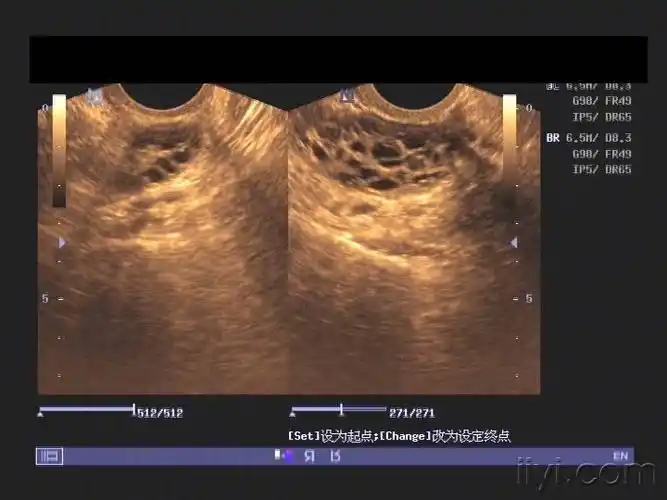

多囊卵巢是b超检查发现卵巢呈多囊样改变:一侧或双侧卵巢直径2-9mm的

3,多囊卵巢,单侧或双侧有大于或等于12个小卵泡.

(双侧卵巢呈多囊样改变)该怎么治?白带拉丝一定排卵吗?